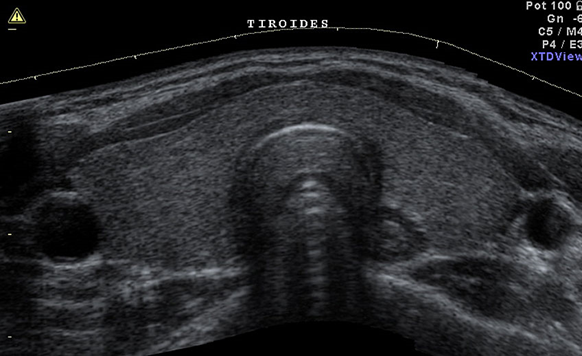

3. Ecografia tiroidea

L’ecografia tiroidea rappresenta lo strumento di riferimento per valutare:

- il volume della ghiandola (utile per il dosaggio del radioiodio);

- la morfologia tiroidea (presenza di noduli, cisti, calcificazioni);

- eventuali segni sospetti per malignità.

È un esame non invasivo, ampiamente disponibile e complementare alla scintigrafia.